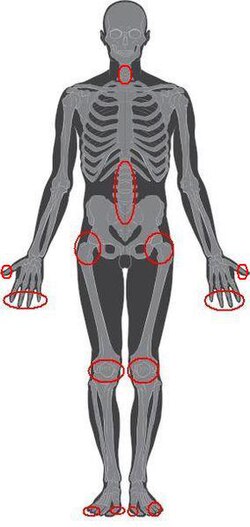

Artroza ili osteoartroza je degenerativna bolest perifernih zglobova. Bolest nastaje kao posljedica degenerativnih promjena u zglobnoj hrskavici, što dovodi do subkondralne skleroze kosti i hipertrofičnih promjena na rubnim dijelovima kosti (osteofiti)[1] Ako bolest zahvati veći broj zglobova tada govorimo o poliartrozi. Artroza je neizlječiva bolest i najčešće se s vremenom pogoršava. Jakost simptoma se međutim može kontrolirati pravilnim i kontinuiranim liječenjem [2] [3].

Artroza (osteoartritis) je najčešća bolest zglobova u svijetu, ne samo među ljudima nego i među životinjama (lumbalni dio kralježnice konja, kuk gorile itd.). Degenerativne promjene nađene su na ostatcima kostura pretpovijesnih životinja i ljudi (mezozoički dinosaur, neandertalski pračovjek, Krapinski čovjek 40.000 pr.Kr.). Učestalost artroza je danas veća od reumatoidnog artritisa i gihta zajedno. Procjene broja oboljelih razlikuju se između različitih populacija. Učestalost artroze različita je među različitim etničkim skupinama [36]. Ovaj je poremećaj učestaliji u Sjevernoameričih Indijanaca a znatno manje u Kineza iz Hong Konga u odnosu na istu starosnu grupu bijelaca [37]. Kod osoba starijih od 65 godina, artroza je češća u bijelaca nego u crnaca. Artroza koljena (gonartroza) je češća kod žena crne rase u odnosu na žene drugih rasa [36]. Artroza pogađa više od 20 milijuna ljudi u Sjedinjenim Američkim Državama, iako se statistički podatci razlikuju ovisno o primjeni epidemiološke metode (npr. primjene radiografskih kriterija) ili kliničkih kriterija (npr. istovremena uporaba radiografskih nalaza i kliničkih simptoma)[36]. Na temelju radiografskih kriterija na hrskavici izoliranih zglobova, degenerativne (artrotične) promjene pojavljuju se kod više od polovine odraslih osoba starijih od 65 godina pod utjecajem ove bolesti [36].